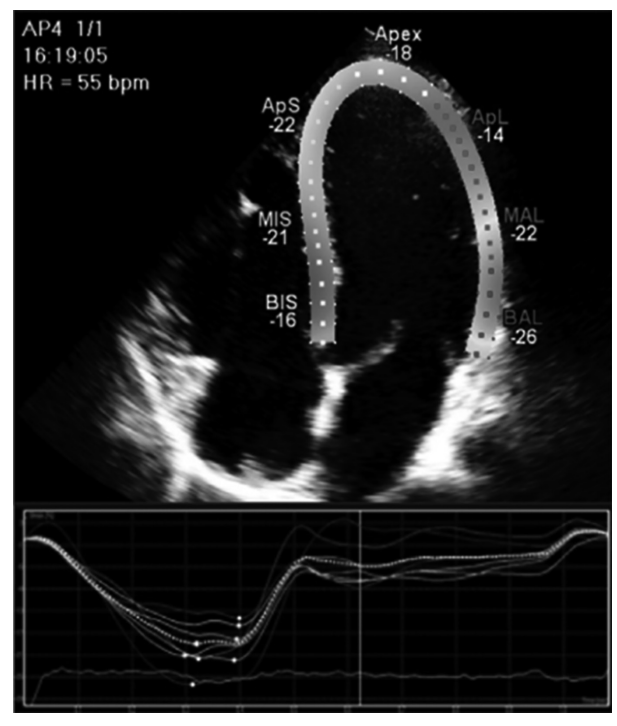

A figura a seguir representa um corte apical quatro câmaras ao ecocardiograma transtorácico mostrando o cálculo do strain global longitudinal (GLS), que descreve a mudança relativa do comprimento do miocárdio do ventrículo esquerdo entre a diástole final e sístole final por meio da fórmula GLS% = (MLs – MLd)/MLd.

Dados: ML: comprimento miocárdico, MLd: comprimento miocárdico diastólico, MLs: comprimento miocárdico sistólico.

Com relação a aspectos relacionados à técnica da captura da imagem cardíaca ao ecocardiograma, é incorreto afirmar: